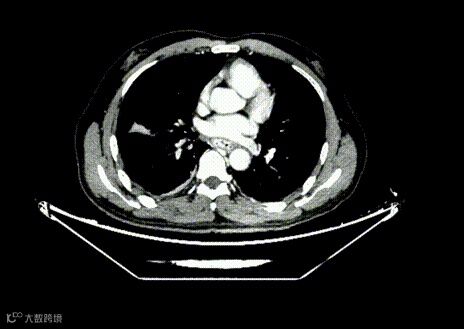

术前影像学检查(术前评估)

CT 全腹平扫+增强

1.肝硬化、食管胃底静脉曲张,胃腔内积血。

2.  肝右叶少许钙化灶。

3.双肺少许小结节,考虑低危结节,必要时随诊复查。

4.双肺尖胸膜下肺大泡。

5.双肺下叶后胸膜下弧形斑片影,坠积效应可能,炎症待消除。